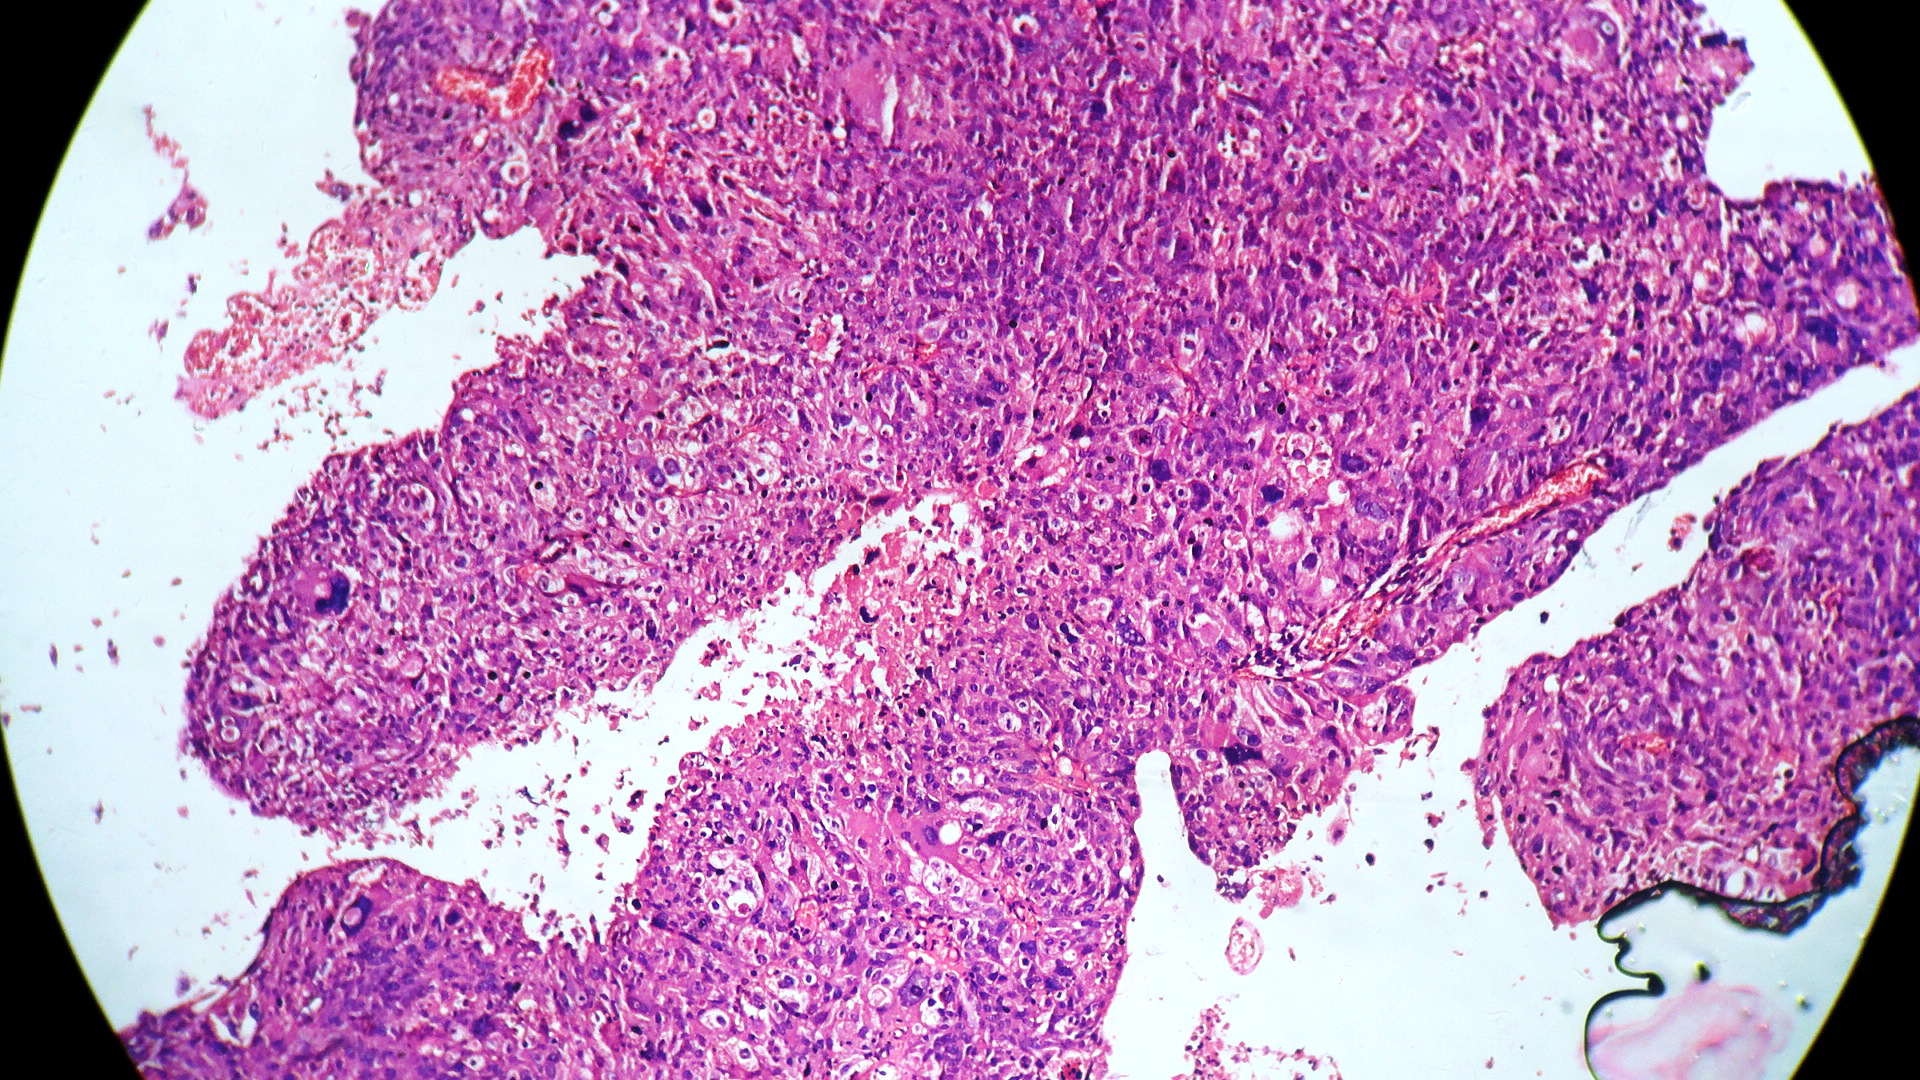

In our study, we made an attempt to evaluate the pattern of tumor growth, its degree of differentiation, progression and associated mucosal changes. In 15 cases of urothelial papilloma, it is characterized by discrete papillary growth with a central fibrovasular core lined by urothelium of normal thickness and cytology (Figure 1). In five cases of Papillary urothelial neoplasm of low grade malignant potential (PUNLMP), histopathologically the tumor is characterized by delicate, orderly, tenuous papillary structures with orderly arrangement of cells within the papillae with minimal architectural abnormalities and nuclear atypia usually limited to basal layer irrespective of cell thickness (Figure 2). The major distinction from papilloma is that in PUNLMP the urothelium is much thicker and nuclei are significantly enlarged. In 21 cases of low grade urothelial carcinoma, histologically it is characterized with papillary axes which are more compact, crowded, fused at the base and lined by unordered cells showing both architectural and cytological abnormalities with frequent mitosis (Figure 3). In 51 cases of high grade urothelial carcinoma showed fused papillary axes over the large areas resulting in sheets and solid areas. The cells have enlarged, hyperchromatic, pleomorphic nucleus in full thickness of the epithelium with increased atypical mitosis (Figure 4). As per TNM staging used in our study we observed majority of the bladder tumours were invasive accounting for 78.25% (Figure 5 & 6) as compared to non-invasive bladder tumours constituting 21.73% of the cases as shown in table 3.